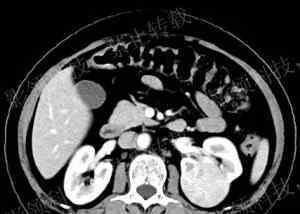

CT平扫及增强:左肾凸起,长实,呈圆形。增强扫描显示快进快出,皮质期增强不均匀,周围有假包膜。

1)病变位于肾皮质,长在肾的轮廓或表面之外,大部分病变突出于肾的轮廓。

2)稍低或等密度病灶,有点状钙化,边缘清晰,包膜完整。

3)病灶中心的星疤是其特征性改变。

4)动态增强后,肿块边缘明显增强,皮质病灶的增强程度甚至可以超过肾皮质,病灶边缘密度随时间延迟而降低,但造影剂趋向于充满中心。